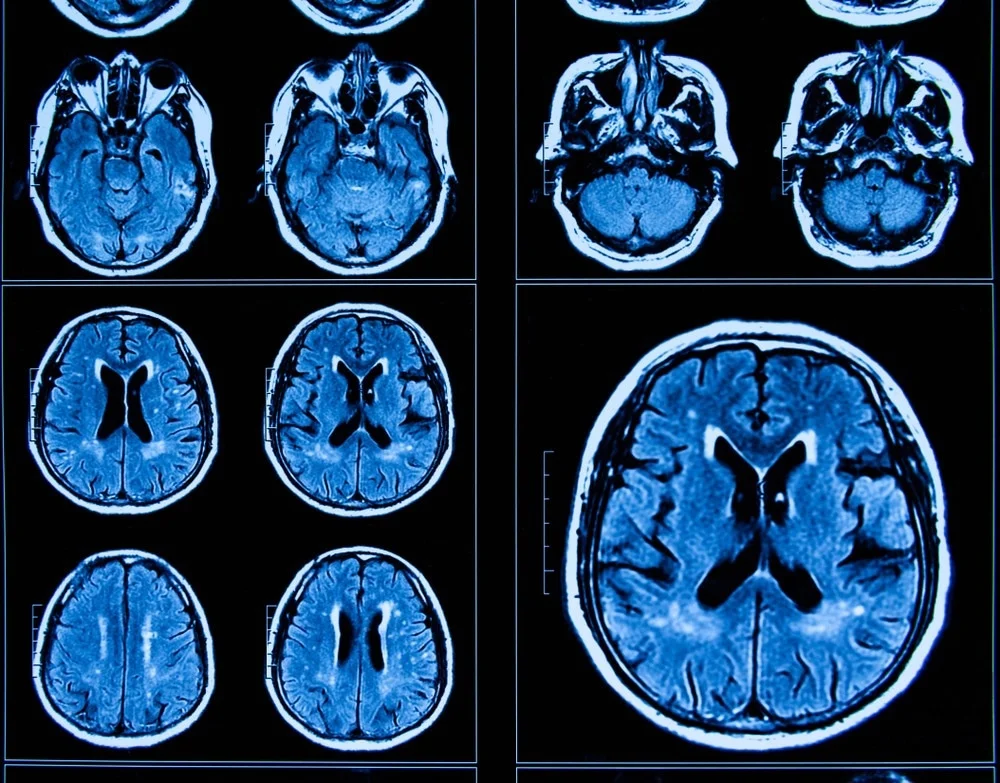

Studiuesit, të udhëhequr nga profesoresha Patricia Kuhl nga Universiteti i Uashingtonit, zbuluan se pandemia gjithashtu shkaktoi hollim të përshpejtuar të korteksit cerebral, shtresa e jashtme e trurit përgjegjëse për funksione të ndryshme njohëse. Ky hollim kortikal ndodh natyrshëm me moshën, por përshpejtohet nga stresi dhe fatkeqësitë kronike, gjë që rrit rrezikun e çrregullimeve psikiatrike dhe të sjelljes si ankthi dhe depresioni, gjendje që janë më të përhapura gjatë adoleshencës dhe veçanërisht prekin femrat.

Studimi filloi fillimisht në vitin 2018 me qëllimin e vlerësimit të ndryshimeve të strukturës së trurit gjatë adoleshencës në 160 të rinj të moshës nga nëntë deri në 17 vjeç. Megjithatë, testet vijuese të planifikuara për vitin 2020 u shtynë deri në vitin 2021 për shkak të pandemisë. Deri atëherë, studiuesit e zhvendosën fokusin e tyre për të vlerësuar se si bllokimet kishin ndikuar në zhvillimin e trurit.

Dr. Neva Corrigan, autori kryesor i studimit, dhe ekipi i saj riekzaminuan pjesëmarrësit, duke përdorur të dhënat e vitit 2018 për të modeluar hollimin e pritshëm të kortikalit gjatë viteve të adoleshencës. Gjetjet e tyre zbuluan se ndërsa hollimi kortikal u përshpejtua te të gjithë adoleshentët, efekti ishte dukshëm më i theksuar tek vajzat, duke prekur të gjitha lobet dhe hemisferat e trurit. Tek djemtë, ndikimi ishte i kufizuar në korteksin vizual.